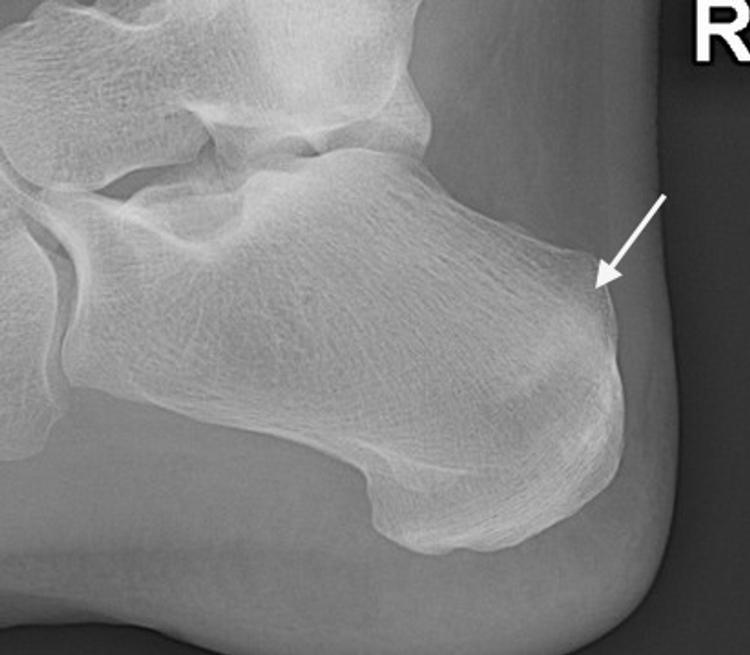

For a stress reaction or dorsal cortex fracture, non-operative treatment with six weeks non-weight-bearing in a plaster may settle down symptoms. In elite sportsmen and for complete fractures then internal fixation may be preferred. If the fracture goes on to non-union and collapse then secondary osteoarthritis will supervene. Calcaneal stress fractures present with a history of heel pain on weight-bearing and no history of trauma. They occur commonly in runners and present with heel pain worse on activity and may also be at night. Examination will reveal tenderness on squeezing the posterior calcaneum. They are misdiagnosed as plantar fasciitis, or Achilles tendinopathy, as the X-ray signs are subtle. X-rays, initially normal, will show a poorly defined sclerotic band through the superior aspect of the calcaneal tuberosity which is perpendicular to the trabecular lines (Figure 8).

Fig 8.jpeg

Figure 8: X-ray showing diffuse sclerotic band of stress fracture calcaneum.

These fractures can also occur in the inferior calcaneum. If suspected, an MRI scan will provide the diagnosis. Treatment is usually non-operative with initial non-weight-bearing followed by protected weight-bearing until the symptoms settle. Stress fractures of the sesamoid bones under the 1st metatarsal head can occur, particularly in dancers going frequently en pointe and in athletes. Patients will present with an insidious onset of pain under the 1st mtp joint during and/or after athletic activities. Pain is relieved by rest. On examination there may be tenderness over the sesamoids accentuated by palpation and hyperextension of the joint. Radiology includes standard foot views along with skyline views of the sesamoids. MRI and CT scans will help differentiate sesamoiditis and bipartite sesamoids from a fracture. Initial treatment is usually non-operative but non-union can occur and require surgery.